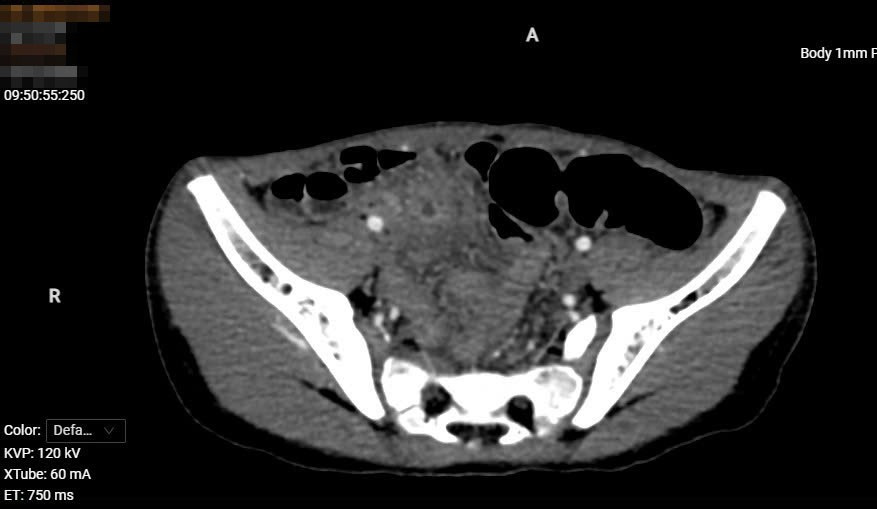

Sau khi bệnh nhân được siêu âm và cắt lớp vi tính thấy: Hố chậu phải có cấu trúc dạng dịch, thành của cấu trúc này có các lớp giống với các lớp của thành ống tiêu hóa, ngấm thuốc mạnh sau tiêm. Dịch bên trong cấu trúc này không đồng nhất. Thành của cấu trúc này có vị trí mất liên tục, thâm nhiễm xung quanh.

Ngay lúc này, bệnh nhân được hội chẩn liên chuyên khoa bởi các bác sĩ Chẩn đoán hình ảnh, Ngoại tổng hợp, Gây mê hồi sức. Bệnh nhân được chẩn đoán viêm phúc mạc khu trú hố chậu phải nghĩ đến nguyên nhân do nang ruột đôi vỡ. Các bác sĩ đã thống nhất thực hiện phẫu thuật mổ cấp cứu cho bệnh nhân.